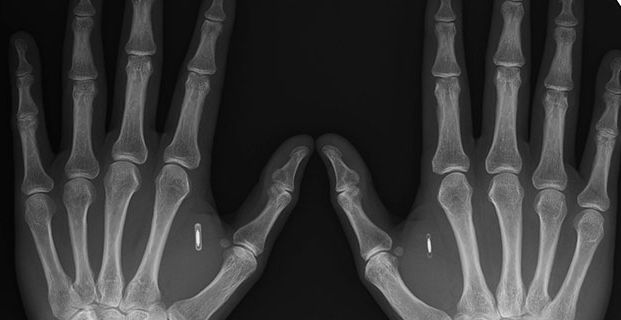

Biohackern Amal Graafstra har opererat in microchp i sina händer – för att underlätta i vardagen. (Foto: Dangerous Things)

Amal Graafstra gör inte som alla andra. Istället för att låsa upp hemdörren, bilen och datorn med nycklar eller lösenord gör han det med inopererade microchip i sina händer. Tekniken bygger på RFID, radio-frequency identification, vilket möjliggör kommunikation mellan transpondrar och minnen, även kallade taggar. Det är sådana taggar som Amal opererat in i sina händer.